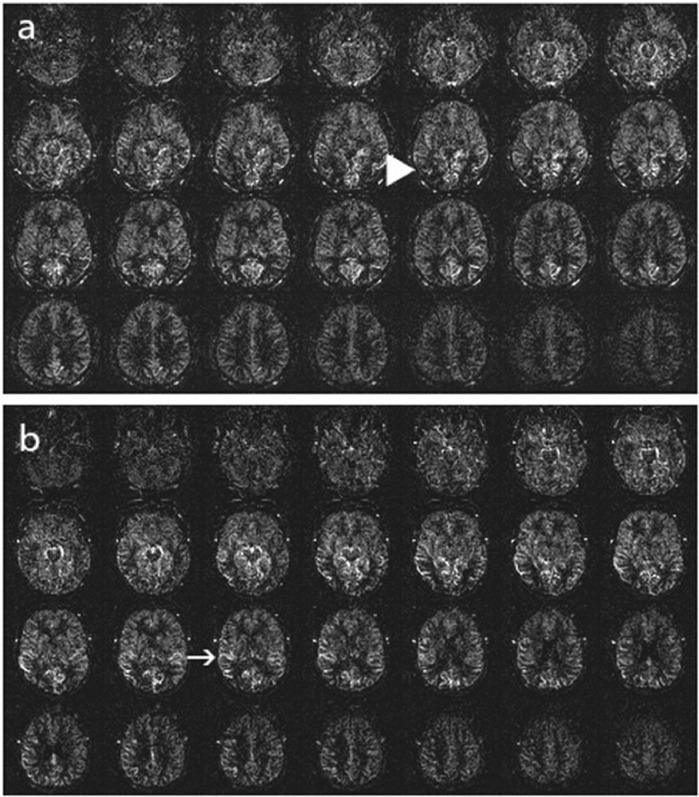

We employed a five-stage scale (0 being normal and 4 indicating the most severe perfusion decline) to assess 156 patients using a 3D pulsed ASL technique. Three radiologists independently reviewed the images, and inter-rater reliability of the visual rating scale was evaluated.

The ASL stages showed a consistent distribution among the patients. The inter-rater reliability among the three radiologists, as measured by the Intraclass Correlation Coefficient (ICC), was 0.982.